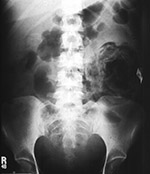

Surgical needles used at University Medical Center, Tucson, AZ. See Hunter, 2010. Surgical blades used at University Medical Center, Tucson, AZ. See Hunter, 2010. Surgical clips and clamps used at University Medical Center Tucson, AZ. See Hunter, 2010. 25 year-old woman who had undergone a Cesarean section in Mexico. She presented with abdominal pain and fever. The abdominal radiograph shows a large complex, partially lucent left flank mass with an associated linear density. At surgery there was a retained surgical sponge with surrounding area of granuloma formation, a gossypiboma. From Hunter, 2003. Permission granted for use of images in this article by Radiological Society of North America (RSNA)